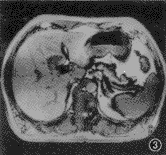

图3,4 患者 男,47岁。肝右叶局灶结节状脂肪浸润,但无占位病变。反相位序列(TR 128 ms,TE 2.7 ms,翻转角70°)示肝右叶低信号结节状脂肪浸润(图3),而在同相位(TR 128 ms,TE 5.3 ms,翻转角70°)上呈等信号(图4)